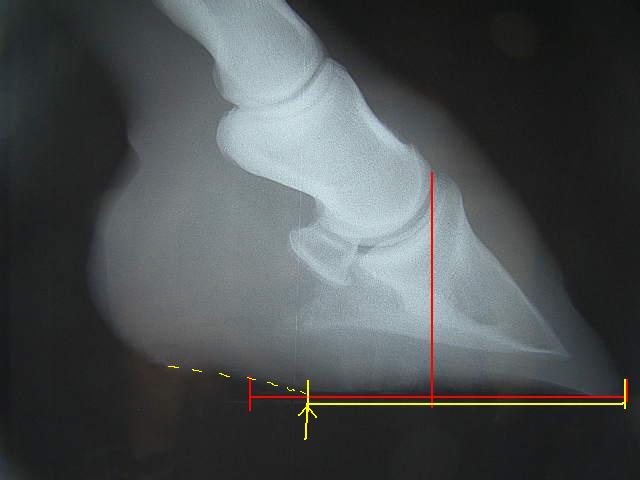

今回の右前肢

こちらも蟻洞がなくなりました。

順調に改善しているのが確認できて本当にホッとしました〜

この写真を参考に、装蹄を行ないました。